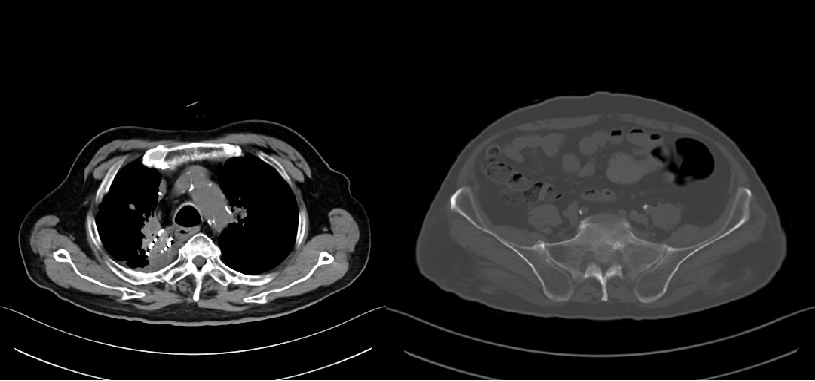

2022年3月,患者至外院住院,拒绝手术,常规口服卡培他滨化疗+右肺病灶放疗(DT 5Gy×11f)。2022-3-30来院复查胸部CT(图2)提示稳定。

2022年5月,患者因咳嗽、气喘来院复查CT(图3)示:放射性肺炎,给予激素、抗炎、平喘等治疗后好转。后多次因肺炎入院给予抗炎、激素、平喘等治疗。

2023年4月,复查胸部CT(图4):符合右肺上叶病变治疗后复查表现,右肺下叶及左肺上叶纤维灶、结节灶,邻近支气管扩张;COPD影像表现,左侧肾上腺结节;右肺上叶肿瘤局部进展。